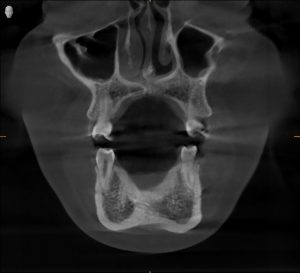

Radiographs confirmed it — his airway was constricted.

His jaw alignment had shifted to make breathing easier, but that adaptation had caused years of TMJ dysfunction.

Clinical & Radiographic Findings

- Forward head posture and low tongue position

- Narrow pharyngeal airway space

TMJ Dysfunction associated with restricted airway and myofunctional imbalance.

Radiographs confirmed increased airway space and balanced joint position.